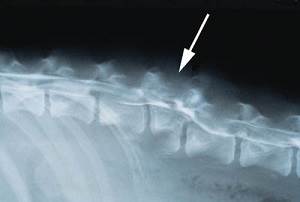

Окончательный диагноз миеломаляция может быть установлен с помощью рентгеноконтрастного исследования спинного мозга (миелографии) или МРТ соответствующего отдела спинного мозга, а также при патологоанатомическом вскрытии. В ряде случаев миеломаляция может быть установлена исходя из клинических симптомов.